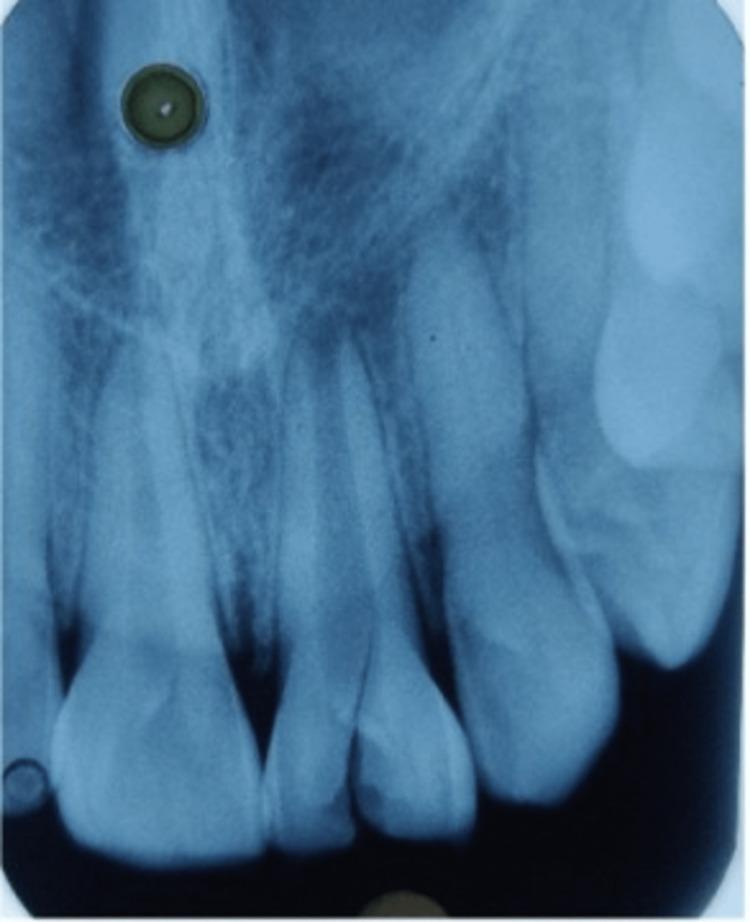

Dental professionals face difficulty in managing "immature non-vital teeth with an open apex." It is considered to be challenging because, in this situation, root canal filling material should be confined within the boundaries of the root canal without extruding peri-apically. Apexification tries to create a hard tissue barrier that will cause the open apex to close, allowing root filling to be compacted. The current case report describes the application of mineral trioxide aggregate (MTA) to create an apical plug in an open apex, as MTA is considered a versatile material for apexification, which was followed by the reinforcing of the weekend root using glass fiber post and core build-up to manage the Ellis class IV fracture.

牙科专业人员在处理“根尖孔开放的未成熟无活力牙”时面临困难。这种情况被认为具有挑战性,因为在这种情况下,根管充填材料应限制在根管边界内,而不会向根尖周挤出。根尖诱导成形术试图形成一个硬组织屏障,使开放的根尖孔闭合,从而能够紧密地进行根管充填。本病例报告描述了使用三氧化矿物凝聚体(MTA)在开放根尖孔处形成根尖屏障的应用,因为MTA被认为是一种用于根尖诱导成形术的多功能材料,随后使用玻璃纤维桩和核桩修复加强薄弱的牙根,以处理埃利斯IV类骨折。